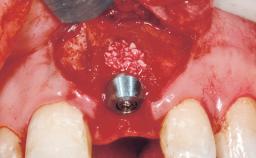

Late Placement of an Implant in a Maxillary Left Central Incisor Site

A 30-year-old female patient had lost tooth 21 and was referred to our clinic for consultation and treatment. Due to advanced apical infection, tooth 21 had been extracted two months earlier at another clinic and an acrylic-resin tooth had been bonded to the adjacent teeth. The patient desired implant treatment to avoid any damage to the adjacent natural teeth. While the patient had no history of any systemic disorder, she was a heavy smoker and exhibited medium to advanced periodontitis in the entire jaw. After the initial treatment to achieve a pocket probing depth of less than 4 mm and no bleeding on probing, a decrease in the height of the papillae mesial and distal to the extraction site and overall gingival recession were observed.

| Bone Augmentation | Horizontal|Staged |

| Augmentation Materials | Autogenous chips|Membrane |